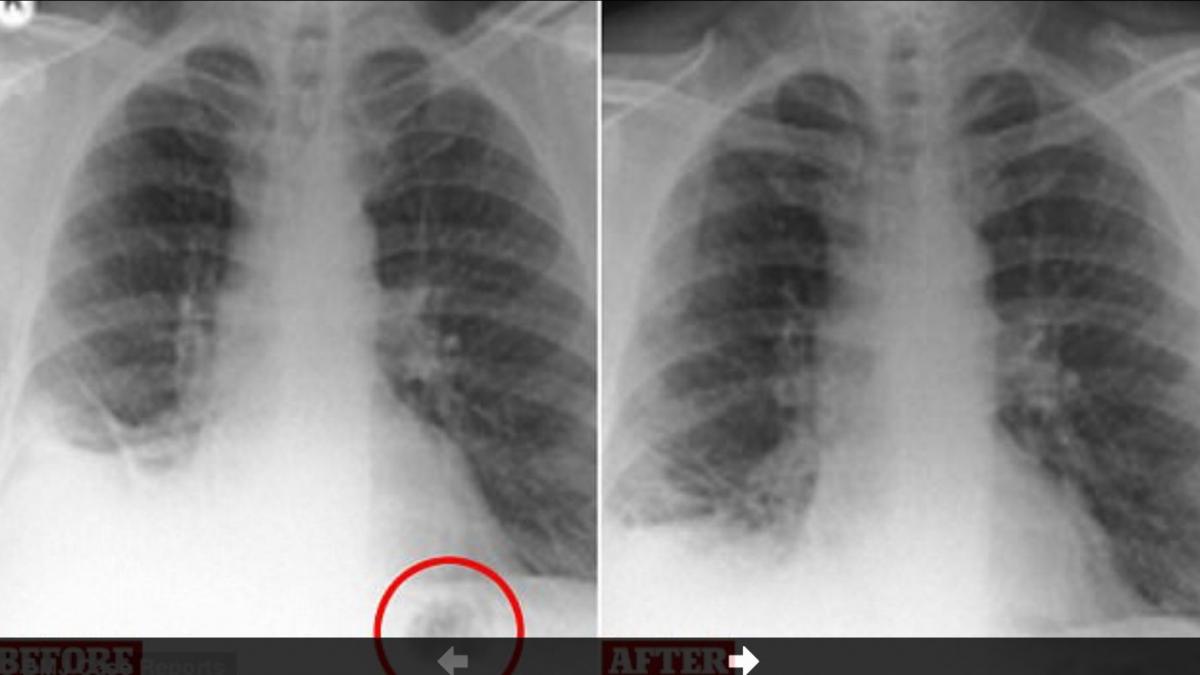

Cum Se Pot Degrada In Trei Zile Plămanii Unui Tanăr De 28 De Ani